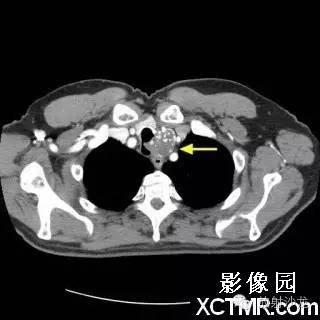

On the contrast-enhanced CT of the chest, there is a heterogeneous mass arising from the left lateral wall of the trachea. The mass demonstrates extratracheal extension as well as extension into the tracheal lumen. (Figure 1 and Figure 2). The mass also contains internal calcifications (arrows), representing chondroid matrix mineralization (Figure 3 and Figure 4).

胸部增强扫描示气管左侧壁发出一不均质的肿块影,肿块向气管内外扩展(图1、2)。其内可见钙化影(箭头),代表软骨基质的钙化(图3、4)。